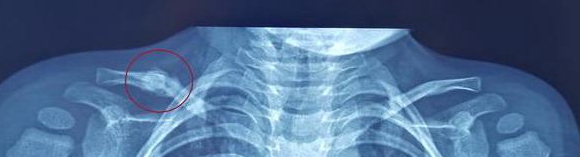

当侧方的冲击力超过锁骨承受的范围时,锁骨就会在应力集中的地方发生骨折。就像那些有担当的人,内心碎成渣渣也不让你看出来。由于大部分人都是首先查看大脑,之后查看四肢,所以,锁骨骨折很容易被忽略和漏诊。

如果姥姥带着皮皮到专业的小儿骨科门诊就诊,通过问诊后医生会轻轻的按压一下锁骨,伴随而来的就是宝宝的剧烈哭闹,医生会给宝宝开具肩部正位的x线检查。

很奇怪,皮皮的x线上没有明显的表现,放射科医生给的报告上说“未见明显骨损伤”,是不是医生的判断出了问题?

但是,皮皮的锁骨压痛的表现肯定是空穴来风(你也可以说不是~~~~),是有原因的。细心如准备行囊的老母亲的小儿骨科医生不会错过任何细微的痕迹。通过仔细查看片子,可以看到,锁骨中间部位的骨皮质有微小的不连续。对,这就是锁骨骨折的x线表现。

皮皮自从就诊后都没有来复诊过,突然有一天,皮皮姥姥带着皮皮大喊着进了诊室“大夫,快看,我外孙这里怎么长了一个大包?硬硬的,不会是肿瘤吧?”让皮皮姥姥更加恼怒的是接诊的任医生很是淡定,就说了一句话“嗯,这是锁骨骨折愈合产生的骨痂,不用担心”。“怎么能不担心呢?长这么大一个包。赶紧给孩子做个检查看看。”正好也到了该复查的日子了,任医生开了锁骨正位片。不到一个小时,结果出来了,果然不出所料。看着锁骨周围像是一层干裂的泥巴样的骨痂,皮皮姥姥终于松了一口气。